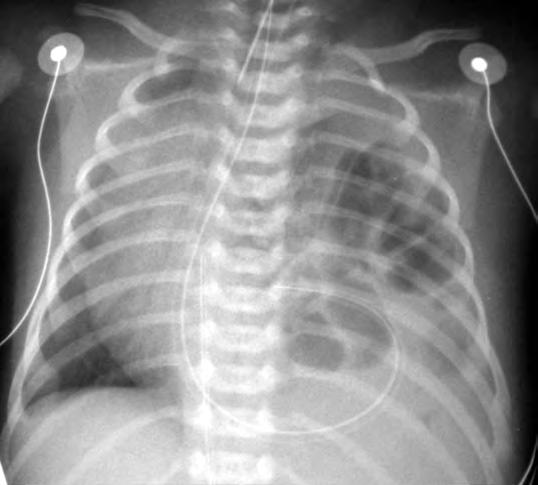

Tras el nacimiento, la observación de abdomen excavado con latido cardiaco desviado en un niño con dificultad respiratoria permite un diagnóstico clínico inmediato y fácil que se confirma con una simple radiografía del tórax en la que se aprecia la desviación mediastínica hacia el lado opuesto a la hernia y la presencia de intestino y/o vísceras macizas en el tórax (Fig. 2.31.1). La ventilación con oxígeno puro proporciona una indicación grosera de la capacidad del lecho pulmonar reducido para permitir una hematosis suficiente si eleva la pO2 rebajando la pCO2 en sangre arterial. Es imprescindible un estudio ecocardiográfico inmediato para detectar la posible participación cardiaca en la malformación. También debe inspeccionarse ecográficamente el aparato genitourinario y buscar en las radiografías anomalías músculoesqueléticas.